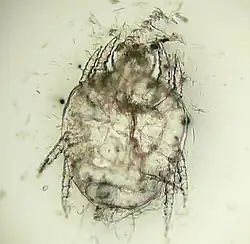

Возбудителем болезни являются клещи Cheyletiella yasguri (Smiley, 1965) и Cheyletiella blakei (Smiley, 1970), которые относятся к типу Arthropoda, кл. Arachnida, отр. Acariformes; п/отр. Trombidiformes, н/сем. Cheyletoidea, сем. Cheyletidae, роду Cheyletiella. Это мелкие клещи овальной формы. Взрослые клещи приблизительно 0.385 мм длиной. Гнатосома у них четко обособлена от тела, имеет вид конуса и плотные покровы. По бокам от неё располагаются крупные щупальца (пальпы) с 5 подвижно соединенными члениками, заканчивающимися когтевидными выростами. Две пары передних конечностей несколько удалены от двух пар задних. Лапки 1 пары ног не имеют коготков. На спинной стороне тела у самок один, а у самцов два гладких трапециевидных щита. Они слабо хитинизированы, желтовато-белого цвета. Краевые щетинки покрыты волосками. У самца половое отверстие расположено в задней половине на спинной стороне тела, а у самки открывается крупной продольной щелью на брюшной стороне.